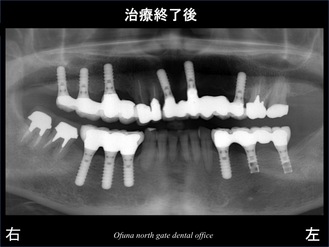

このレントゲンは、デジタルレントゲンです。

その前のレントゲンと比較するとかなり違うのが分かります。

デジタルレントゲンは、現在の大船駅北口歯科で撮影したものです。

噛み合わせは、真っ直ぐになりました。

また、下顎左側の奥2本のインプラントは、初診時にすでに治療をしてあったインプラントです。

他歯科医院で行ったものですが、そのインプラントもそのまま利用しています。

下顎左側のインプラントは、私が使用しているストローマンインプラント(ITIインプラント) と同じメーカーですが、かなり古いタイプであり、現在は使用されていません。